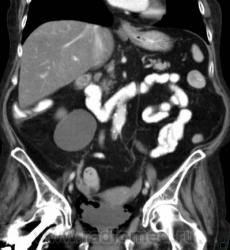

О чём могут говорить такие "газовые структуры" в области мочевого пузыря?

Наличие газа в мочевом пузыре может говорить о многом. Например стоял катетр Фолея, состояние после цистоскопии, эмфизематозный цистит, наличие фистулы.

А, чем именно, будет характеризоваться эмфизематозный цистит? При нем "пузырьки газа" локализуются в слизистой оболочке или где?

В просвете, может быть и в самой стенке. Смотрите здесь:

процесс в стенке в данном случае.

У женщины киста правой почки, подозрение на жировой гепатоз, стержень в головке и шейке правого бедра (остеосинтез). А про воздух возле/в стенке мочевого пузыря... не было ли оперативного вмешательства в малом тазу? И без аксиальных срезов явно я бы не сказала, где конкретно воздухblush...

Фик с ней с кистой... И какая разница аксиалы и короналы... Да, толстоваты срезы, эффект усреднения. Но я бы думал в сторону язвенного/гангренозного цистита (эмфизематозного цистита). Естественно, анамнез и клиника и всё встанет на свои места. На состояние после катерера не очень похоже...

А может, и тут свищ, как в случае Марио на радиографии... Валентин Львович, а что всё-таки с клиникой?

Клиники не знаю, коллеги из ОКБ поделились "изображением". Мне стало интересно, так как при обычной рентгенографии (обзорной), да и внутривенной, такое вряд-ли можно увидеть, вот я и решил поделиться...

Но, свища точно нет.